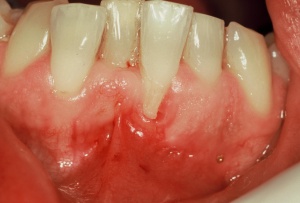

Wie einzelne zahnmedizinische Fachdisziplinen interagierend im klinischen Alltag gekoppelt sein sollten und welche Relevanz diesem interdisziplinären Aspekt zukommt, wird anhand einer Kasuistik mit einem Krankheitsverlauf von über drei Jahren verdeutlicht. Chronische destruktive Erkrankungen wie die Parodontitis, deren unmittelbare und weitläufige Effekte kardinale Folgen für jegliche weitere Therapieschritte haben, müssen nicht nur fachlich korrekt durchgeführt werden, sondern sicher und erfolgreich abgeschlossen sein. Zeitfenster für die Rekonvaleszenz oralchirurgischer und implantologischer Therapiephasen können effizient genutzt werden. Damit ein therapeutischer Planungsentwurf valide und zuverlässig zum anvisierten Ziel führt, ist nicht nur eine fachliche Expertise in vielen Teilbereichen der Zahnmedizin notwendig, sondern auch ein motivierbarer Patient, der intrinsisch agiert.

Eine erfolgreiche und nachhaltige zahnmedizinische Rehabilitation ist allein durch die zielorientierte Koordination aller beteiligten Fachdisziplinen realisierbar. Die zahlreichen Interaktionen der zahntragenden Gewebe, der kompletten Mundhöhle mitsamt den Übergängen zu benachbarten anatomischen Strukturen und deren physiologischen Funktionen zeigen, dass eine langfristig erfolgreiche, zahnerhaltende Lösung nur integrativ angegangen werden kann.